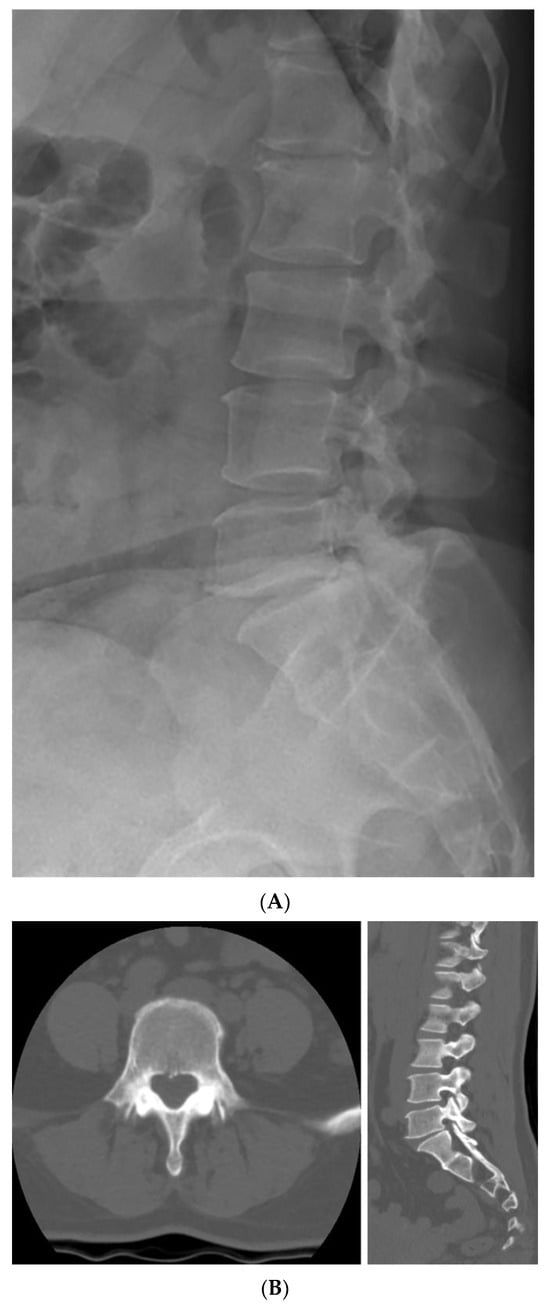

Further imaging evaluation was performed to confirm the previously diagnosed L5 bilateral pedicle fracture and to assess the involvement of surrounding structures. Figure 1A shows a plain radiograph taken during the initial examination in our hospital, revealing a subtly visible fracture at the pedicle of L5 and suspicious Meyerding grade 1 spondylolisthesis at the L5-S1 vertebrae. As shown in Figure 1B, dynamic flexion-extension lateral radiographs were performed to assess instability that could affect the treatment approach, and no abnormal findings were observed. Figure 1C shows a CT scan confirming isolated bilateral pedicle fractures at L5, consistent with the findings from the previous examination at the local clinic, and no additional fractures were identified. There were no sclerotic changes surrounding the fracture lines or pseudoarthrosis, suggesting an acute fracture despite the absence of recent trauma history. Pars defects or hypoplastic neural arch were not observed. Figure 2 shows MRI findings demonstrating low signal intensity on T1 and T2 weighted images in the bilateral pedicle lesions, consistent with acute lesions, and minimal hyperintense marrow edema surrounding the fracture lines on T2. Additionally, imaging revealed mild degenerative changes, including disc bulging at L3–4, L4–5, and L5–S1, and Modic type 2 at L5–S1. These disc lesions showed no features suggestive of an acute rupture and were more compatible with chronic degenerative changes rather than acute pathology. Given the absence of pre-existing LBP or neurologic symptoms, these degenerative findings were regarded as incidental and unrelated to the patient’s current presentation.

Figure 1. Initial radiologic evaluation at the first visit to our hospital. (A) The image shows a subtly visible fracture at the pedicle of L5 and Meyerding grade 1 spondylolisthesis at the L5–S1 level. (B) Flexion–extension lateral radiographs showing no relative sagittal plane translation between L5 and S1. (C) CT images confirming isolated bilateral pedicle fractures at L5 without additional fractures. No sclerotic change, pseudoarthrosis, or pars defect was observed, consistent with an acute fracture.